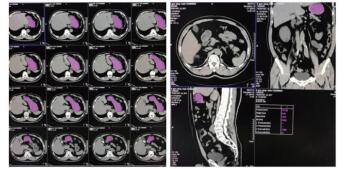

1.3 CT计算胃残余量和超声测定胃窦截面积⑴CT计算胃残余量:使用64排128层4D螺旋CT机(SOMATOM Definition AS型,德国SIEMENS公司)进行腹部CT检查,然后利用VOLUME-Work Flow医学图像软件(德国SIEMENS公司)对CT图像进行分析,即以Freehand方式对胃进行描记,从胃底开始逐层勾画胃壁轮廓形态并进行修正,以及设置CT评估限值,最终通过软件自动计算出胃腔总容积、胃腔气体容积、胃腔非气体容积及胃腔容积高度,其中胃腔非气体容积为患者胃残余量值(见图 1)。

| 图 1 CT检测胃容积的方法(左:描计胃轮廓;右:胃残余量计算) Fig 1 The capacity of stomach measured by CT (Left, the tracing of gastric outline; Right, the calculation of gastric residual volume) |

⑵超声测定截面积:由一位接受过急危重症超声规范培训的医师完成。使用M9便携式彩色多普勒超声诊断仪(深圳迈瑞公司),选择低频曲阵探头、频率2~5 MHz、标准腹部模式,患者分别于半坐位、平卧位与右侧卧位三种体位,探头置于上腹部矢状位或旁矢状位扫描,以腹主动脉、肠系膜上动静脉为定位标志获取胃窦图像,应用自由追踪描记技术描记胃窦截面的轮廓范围,取三次测量数据的平均值后计算胃窦截面积(见图 2)。

| 图 2 床旁超声检测胃窦截面积的方法(左:探头位置;右:胃窦截面轮廓描记) Fig 2 The cross-sectional area of gastric antrum measured by bedside ultrasound (Left, probe position; Right, outline tracing of gastric antrum cross-section) |